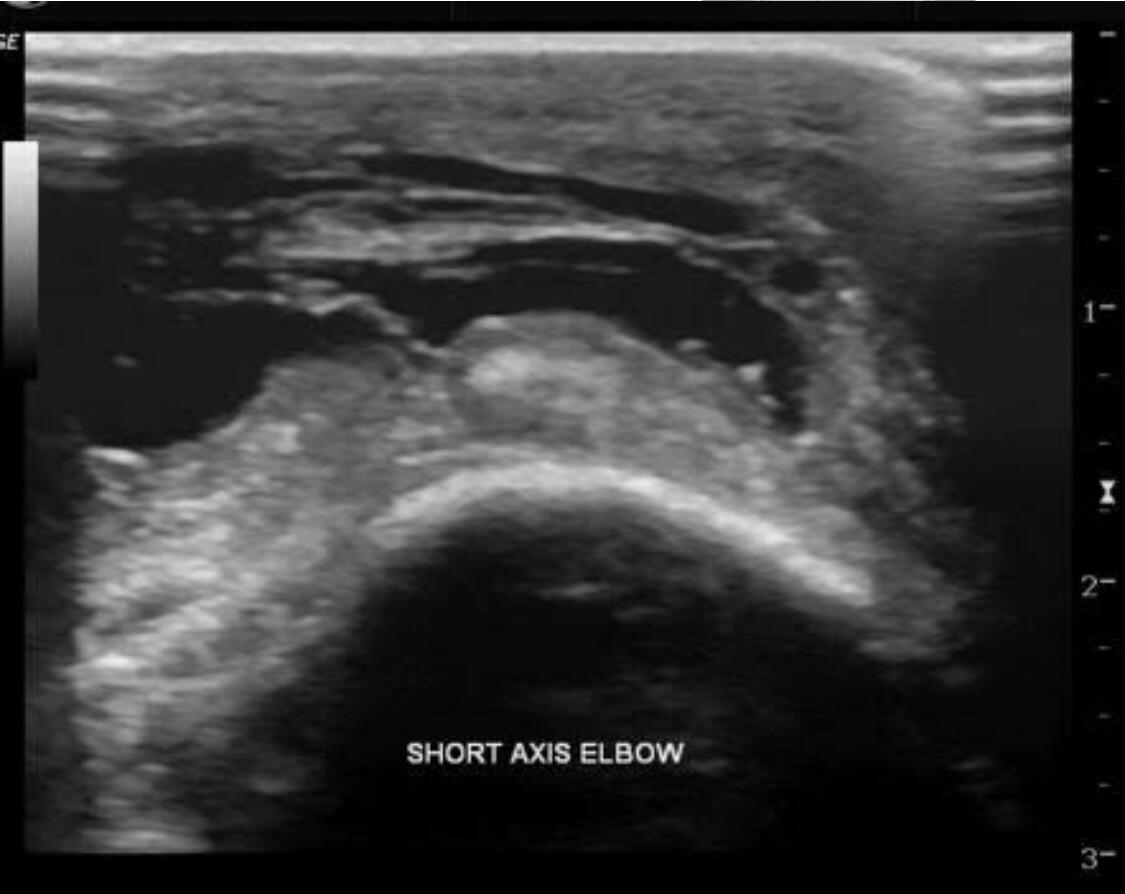

Olecranon bursitis refers to inflammation of the olecranon bursa. The olecranon bursa is a subcutaneous space lined with a synovial membrane that secretes fluid to provide smooth and almost frictionless motion between the skin, the subcutaneous tissues, and the olecranon. Because of its superficial location, it is a common site for injury, inflammation, and infection. Repeated traumatization of the elbows at work led to common terms for different forms of occupational bursitis such as “student's elbow” or “miner's elbow”.

Approximately one third of the cases of olecranon bursitis are septic. Many patients with septic olecranon bursitis lack a history of trauma or a visible injury over the olecranon.

Lateral radiograph of the elbow reveals soft tissue swelling superficial to the olecranon. Ultrasound may show a fluid collection in the olecranon bursa, features of synovial proliferation and/or hyperemia.

CT will show fluid density at the subcutaneous tissue superficial to the elbow. Bursal fluid collection in MRI has the following features: hypointense-T1, mainly hyperintense-T2, and enhancement of bursal margins in post contrast imaging.